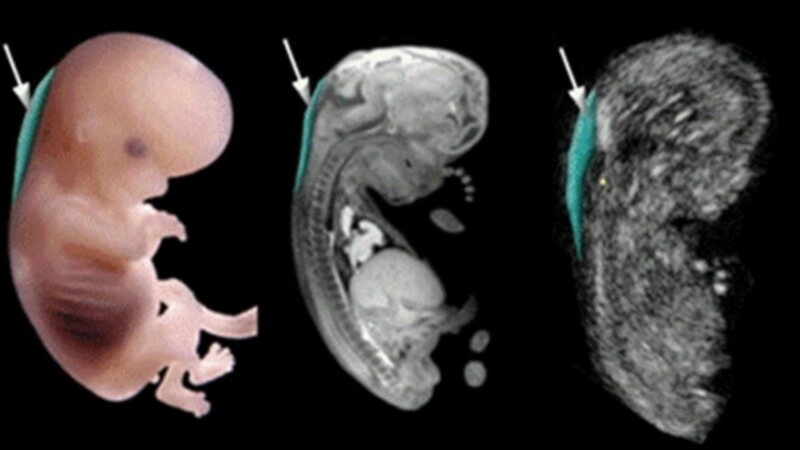

Siêu âm độ mờ da gáy là một trong những cách kiểm tra cổ thai nhi khi thai được khoảng 11 đến 13 tuần 6 ngày, hoặc khi chiều dài đầu và xương chậu của thai nhi đạt 45 - 84 mm. Tên tiếng Anh của kỹ thuật này là Nuchal Translucency, thường được viết tắt là NT.

Độ mờ da gáy là sự tích tụ chất lỏng dưới da ở phía sau cổ của thai nhi. Tất cả thai nhi khỏe mạnh đều có chất lỏng ở cổ, nhưng thai nhi mắc hội chứng Down và một số bất thường nhiễm sắc thể khác thì chất lỏng này tăng lên bất thường. Vì vậy, siêu âm độ mờ da gáy là một cách để chẩn đoán và kiểm tra thai nhi về hội chứng Down và bất thường nhiễm sắc thể ở giai đoạn sớm.

Cách siêu âm đo độ mờ da gáy

Siêu âm đo độ mờ da gáy là một thủ thuật an toàn, bác sĩ sẽ đặt một thiết bị siêu âm trên bụng mẹ để xác định tuổi thai, ngày dự sinh và đo độ dài đầu mông của thai nhi. Nếu thai phụ quá béo hoặc có tử cung nghiêng về sau, bác sĩ sẽ tiến hành siêu âm đầu dò để thu được kết quả chính xác nhất. Sau đó, bác sĩ sẽ tiến hành đo độ mờ da gáy, khoảng mờ này là một đường trắng xuất hiện sau gáy, khu vực xung quanh đó có màu tối hơn. Thực hiện 3 lần đo và lấy kết quả đo lớn nhất.

Trong lần siêu âm này, bạn có thể nhìn thấy các bộ phận của con như chân, tay, đầu, xương sống. Những bất thường ở bụng hay hộp sọ của thai nhi cũng có thể được phát hiện.